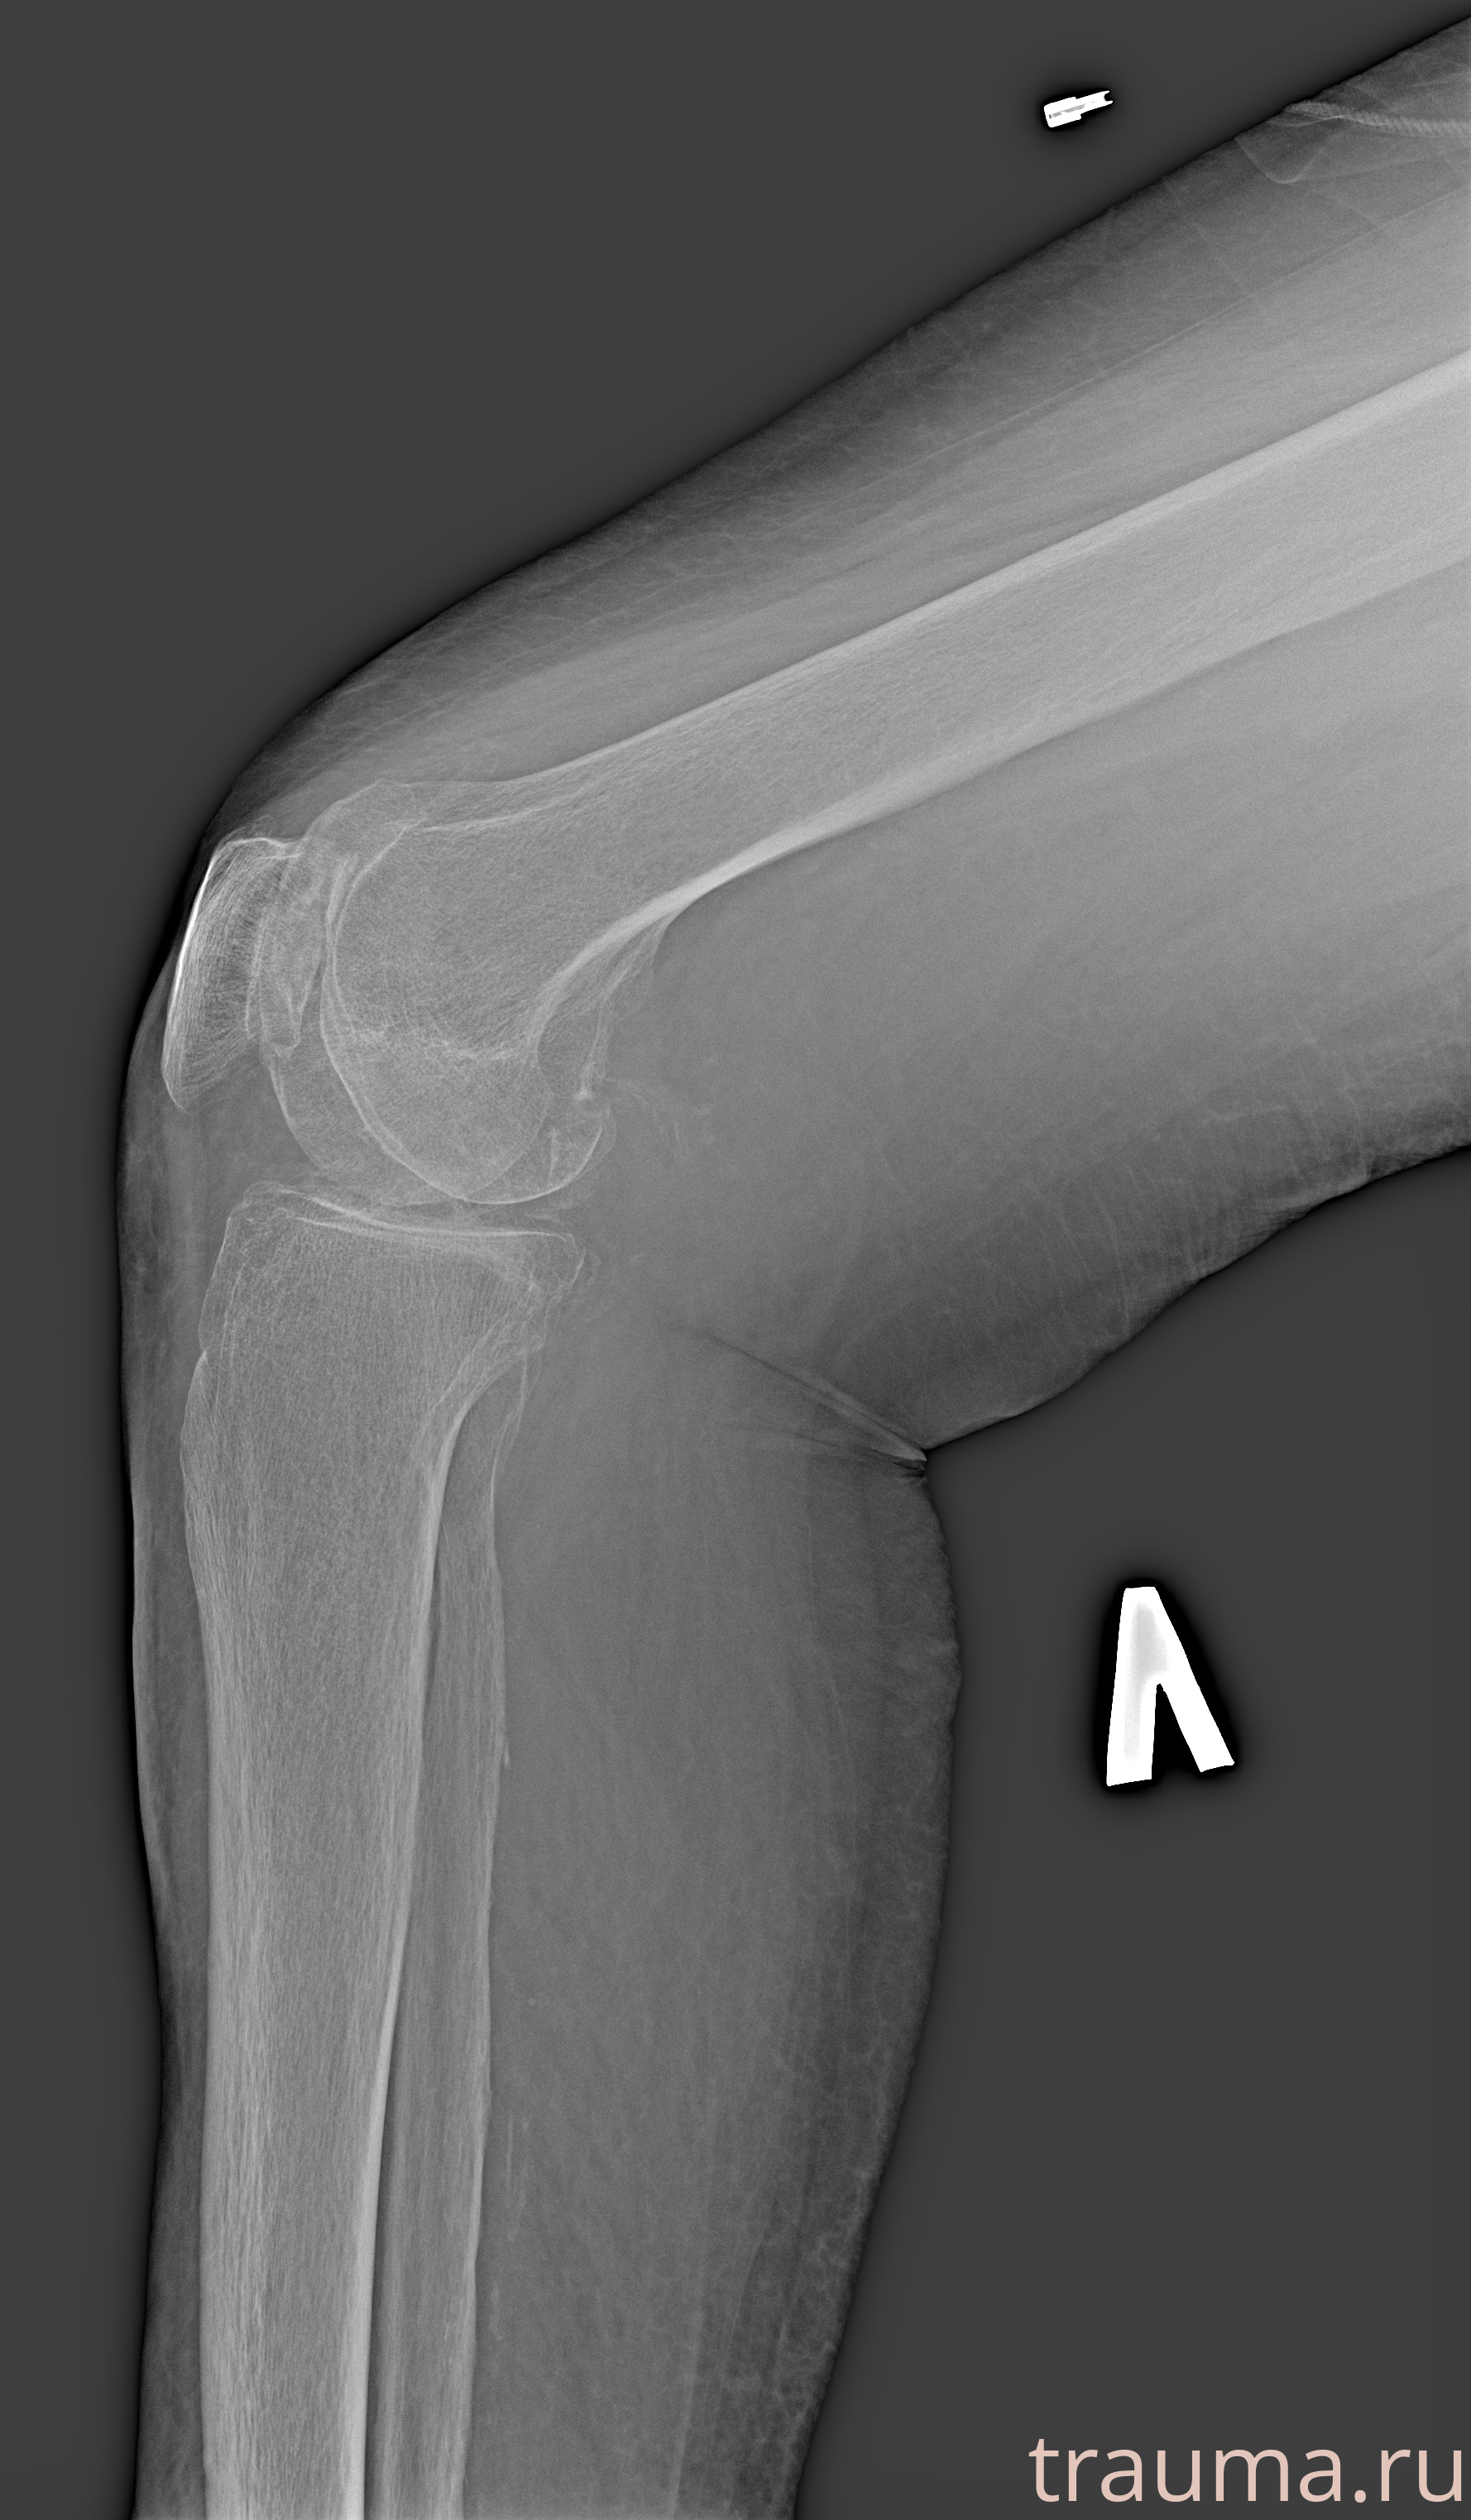

Рентгенограммы

Рентген на дому: по вашему адресу приезжает врач-рентгенолог, травматолог-ортопед с мобильным рентгеновским аппаратом, проводит диагностику травмы или заболевания, делает необходимые рентгенограммы, дает рекомендации по дальнейшему лечению. Получить качественные снимки в домашних условиях возможно благодаря уникальной методике, разработанной МосРентген Центром для института  Склифосовского